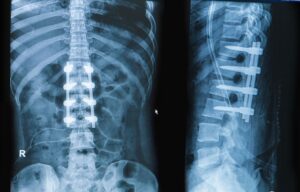

إصلاح تشوهات العمود الفقري

تشمل هذه الجراحات علاج الجنف (انحناء العمود الفقري) والتشوهات الأخرى التي تؤثر على استقامة العمود الفقري.

زراعة الأقراص الفقرية الصناعية

تهدف هذه الجراحة إلى استبدال الأقراص التالفة بأخرى صناعية للحفاظ على الحركة الطبيعية للعمود الفقري.